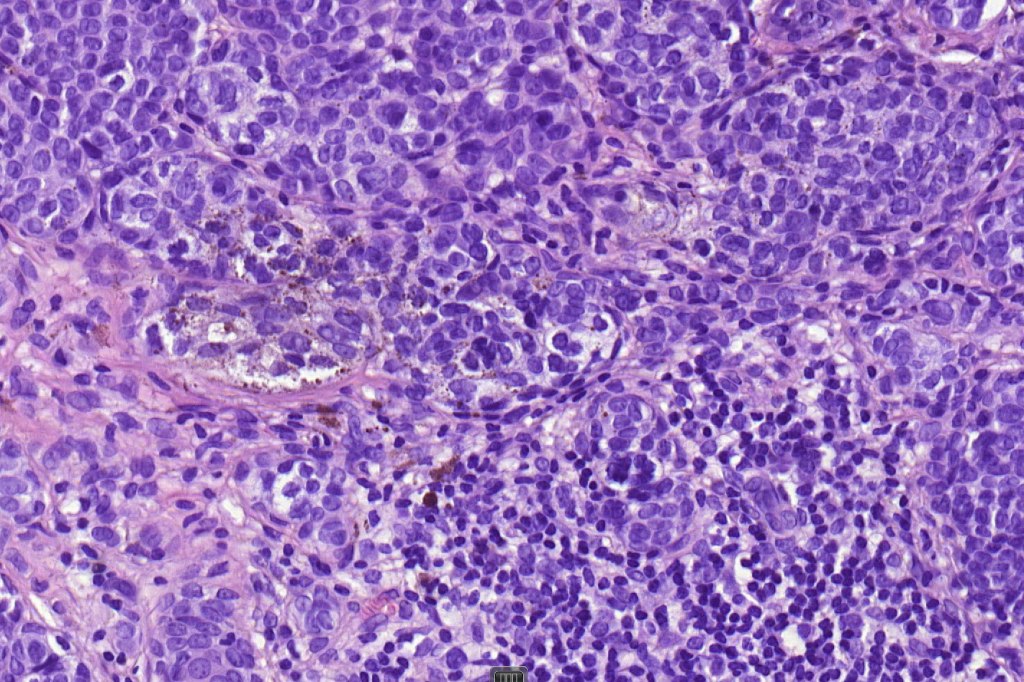

•Usually compound nevus with intense infiltration by lymphocytes, histiocytes and occasional plasma cells, in particularly florrid examples immunohistchemistry may be necessary to identify the nevus cells

•CD8+ve>CD4+

•CD20 +ve to a much minor extent

. Sometimes prominent numbers of Langerhans cell

•Nevus cells often show degenerative atypia (nuclear pleomorphism, hyperchomatism & sometimes fine granular pigmentation (gray or gray/green)

•Melanophages present particularly in older lesions

•Mitoses can be seen in the lymphocytes but not the nevus cells